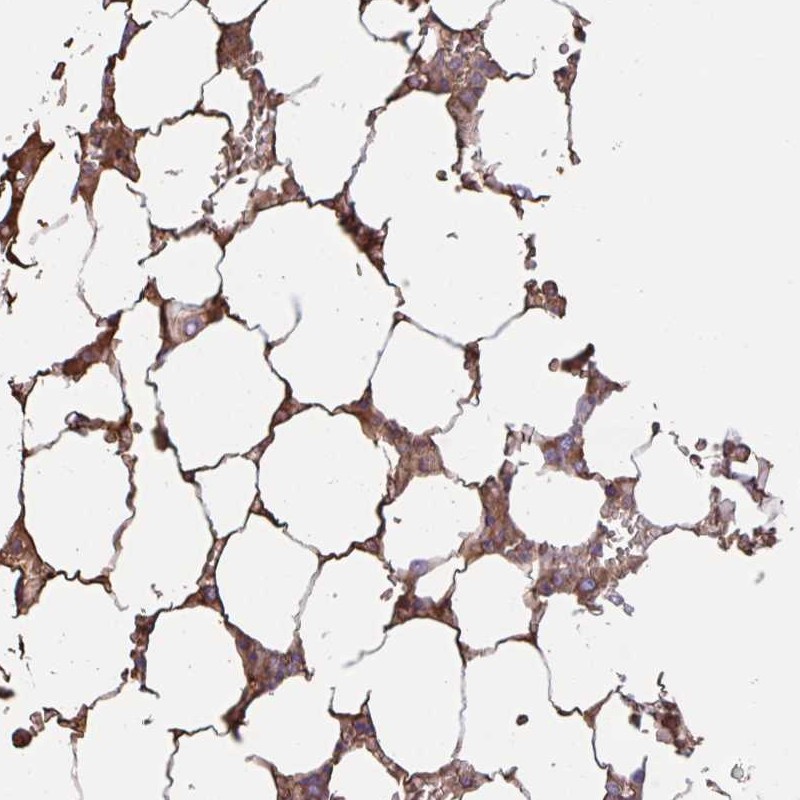

Immunohistochemical staining of human bone marrow shows moderate cytoplasmic positivity in subset of hematopoietic cells.